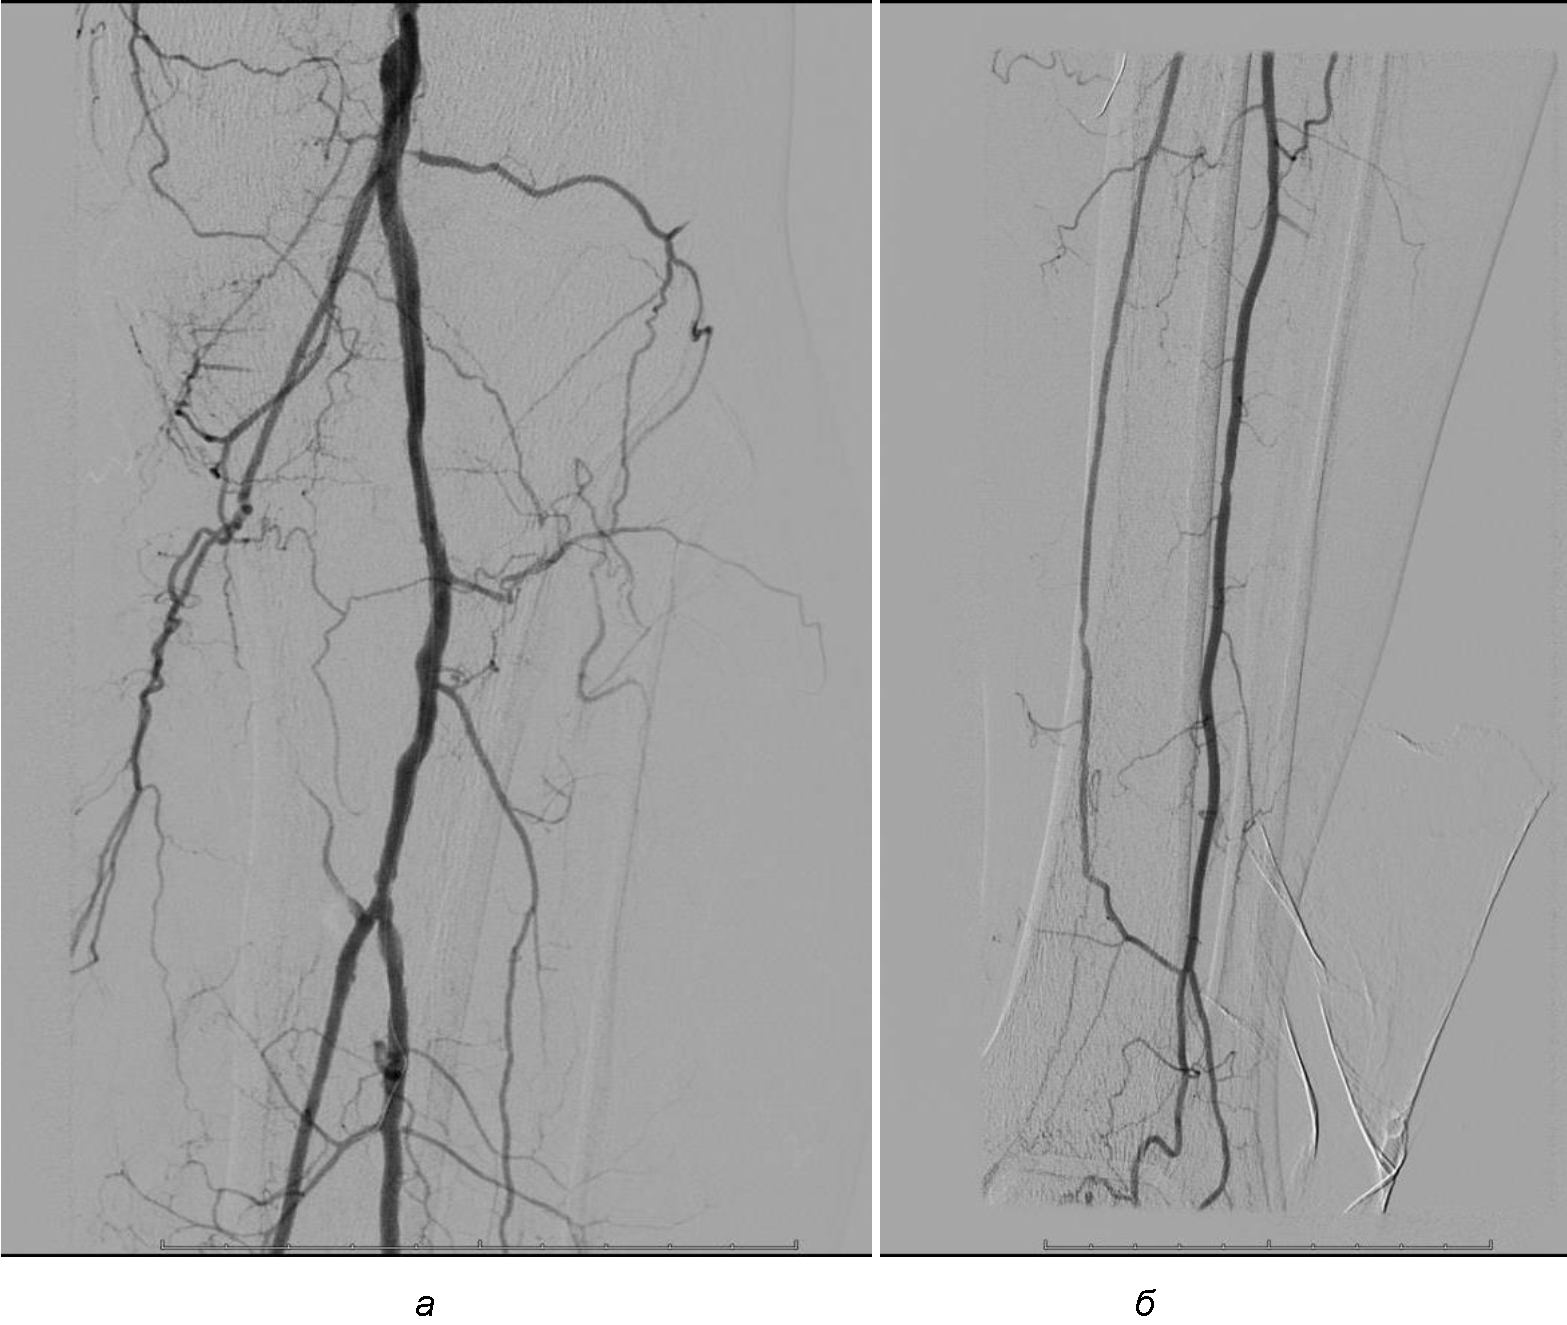

Операция. Транслюминальная баллонная ангиопластика (ТЛБАП) подколенной артерии, тибиоперонеального ствола слева. Под м/а выполнена пункция левой бедренной артерии, установлен интродьюсер 6 Fr. Выполнена селективная ангиграфия артерий левой нижней конечности при которой выявлена субокклюзия подколенной артерии и окклюзия тибиоперонеального ствола (рис. 1). Выполнена ТЛБАП в зоне субокклюзии баллоном 5,0 × 40 мм, давление 8 атм. В области тибиоперонеального ствола ТДБАП баллоном 3,0 мм × 100 мм, давление 10 атм. Получен хороший антеградный кровоток в подколенной, заднебольшеберцовой и малоберцовой артериях (рис. 2). Передняя большеберцовая артерия окклюзирована.

Рис. 1. Ангиограмма больной М. до ангиопластики. Стеноз подколенной артерии (прерывистая стрелка). Окклюзия артерий голени (сплошная стрелка)

Рис. 2. Ангиограмма больной М. после ангиопластики. Восстановление магистрального кровотока в проксимальном (а) и дистальном (б) отделах голени